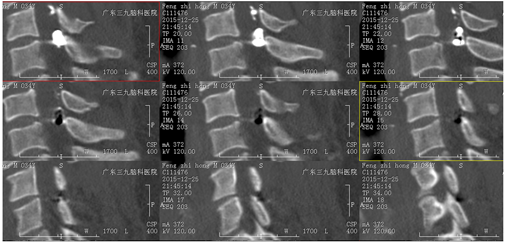

颈4-6水平脊髓内(偏右后部)病变及延髓至颈6水平脊髓周缘线状强化影,考虑为动静脉畸形,并颈髓水肿。

栓塞后CT显示颈4-6水平(偏右后部)栓塞材料高密度影。